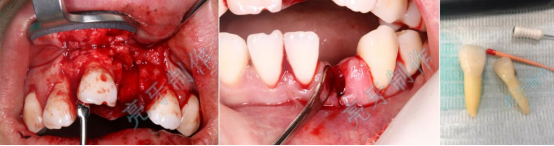

病例三:牙齿嵌入牙槽骨,松动明显,经过治疗,稳定了,也恢复了外形。